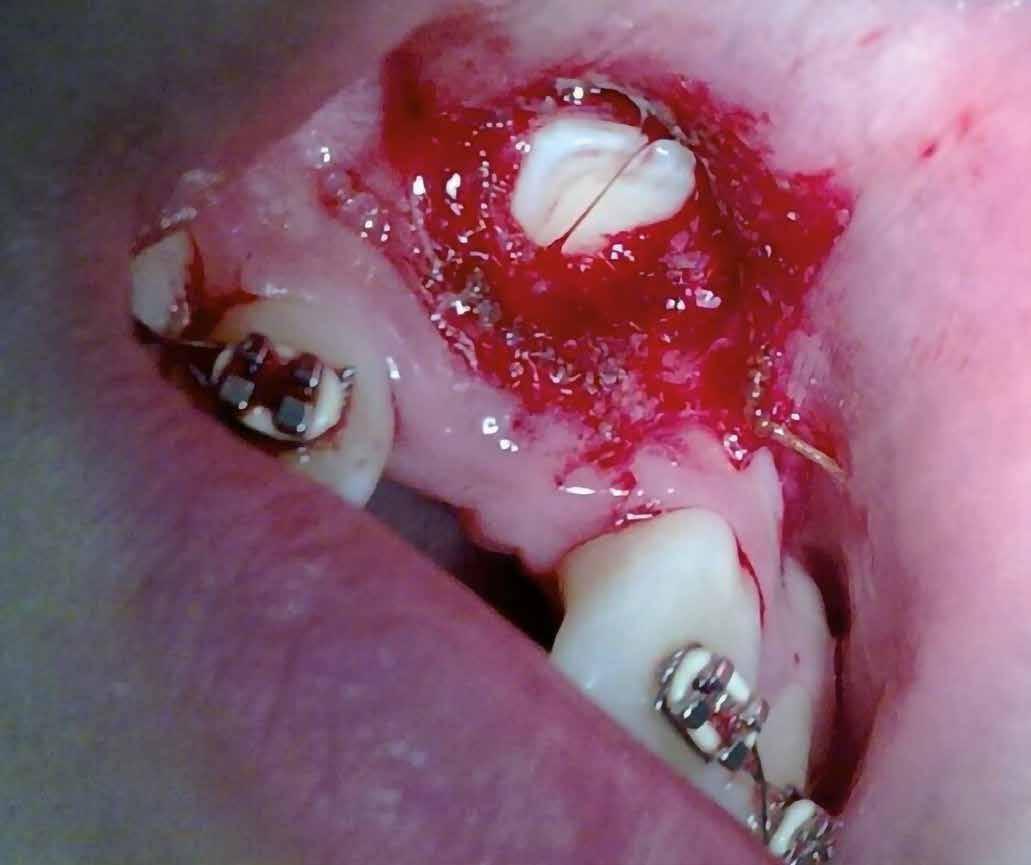

sok korrigálása, valamint az impaktálódott fog előtöréséhez szükséges hely megteremtését követően, egy merev acél ív segítségével stabilizáltuk a fogakat. Ezt követően elvégeztük a jobb felső nagymetszőfog sebészi feltárását. A fog koronáját csupán lágyrész borította, ezért nem volt szükség a csontállomány elvételére. A felszabadítás során egy 975

nm-es hullámhosszon pulzáló üzemmódban alkalmazott lézert használtunk (LaserHF standard, Hager & Werken). A teljesítménye 3 W, az aktív ciklus-idő 50%-os, a vezetőszál átmérője pedig 0,4 mm volt (2. ábra). A lézert 150 másodpercen keresztül alkalmaztuk. A fogat borító lágyrészek eltávolítását követően egy láncos brekettet rögzítettünk a metszőfog bukkális felszínére. A műtétet követően nem tapasztaltunk vérzést, nem alakult ki oedema, valamint a páciens sem számolt be fájdalom vagy bármely egyéb kellemetlenség fennállásáról. A felszabadítást követően a páciens minden hónapban háromszor jelent meg a felszabadított területre ránövő lágyrészek és az íny lézeres eltávolítása céljából. A beavatkozások során ugyanazt a lézer készüléket használtuk, mint amivel a felszabadítást végeztük. Közvetlenül a felszabadítást követően megkezdtük a fog finom extrudálását a láncos breketthez kötött füzérgumi segítségével.

2. ábra: Az impaktált fog lézerrel asszisztált sebészi feltárása. 3. ábra: A kezelés megkezdését követő 15. hónapban megfigyelhető a sikeres felszabadítást, fogmozgatást és pozicionálást követően látható állapot.